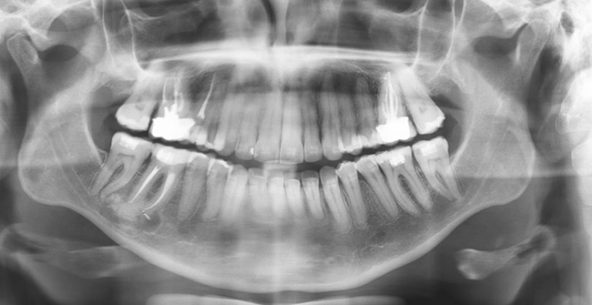

RADIOGRAFIA PANORÂMICA